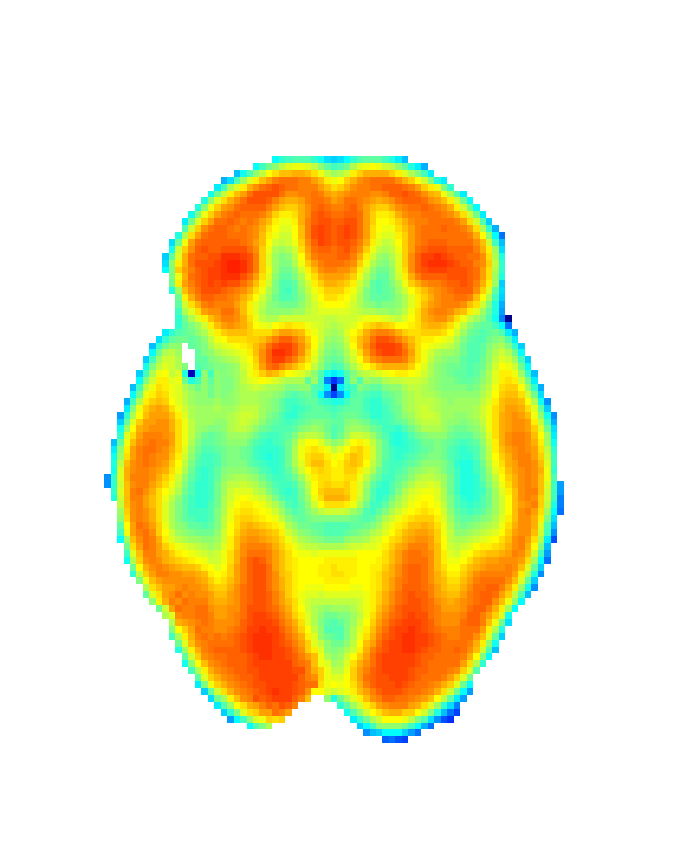

In order to obtain 18F-FDG PET data we drawn upon the Alzheimer’s Disease Neuroimaging Initiative (ADNI) [56], a platform that collects data from different research institutions focusing on AD diagnosis. We selected 18F-FDG PET and MRI data, together with demographic information (age and sex) for CN group (75 patients; 44 male; age: 75.56±4.96plus-or-minus75.564.9675.56\pm 4.96 years) and AD group (51 patients; 30 male; age: 74.03±7.25plus-or-minus74.037.2574.03\pm 7.25 years) summing 126 participants. Images were then realigned, unwrapped, co-registered with MRI data, spatially normalised, mean proportionally scaled, and masked following standard procedures deployed by SPM with the aim of guaranteeing voxel-to-voxel comparability between images (see Figure 2).

Refer to caption

(a) Raw image

(b) Normalized image

(c) Masked image

Figure 2: Stages of 18F-FDG PET processing. (a) Raw image obtained from ADNI, (b) image after anatomical standardization, (c) processed image after masking.